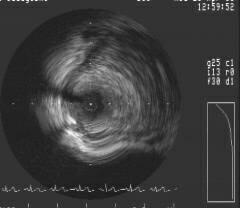

post IVUSありますので、後ほどアップいたします。追加説明ですが、病変にかけた

バルーンとprotectionバルーンの間にちょうどわいてきたように血栓像がでてきまし

た。最終的にはスロンバスターで吸引して消失しました。吸引した中身は、白色血栓

様でした。ちなみに○○先生の症例のようにprotectionバルーンには血栓は付着して

いませんでした。宜しくご教授願います。